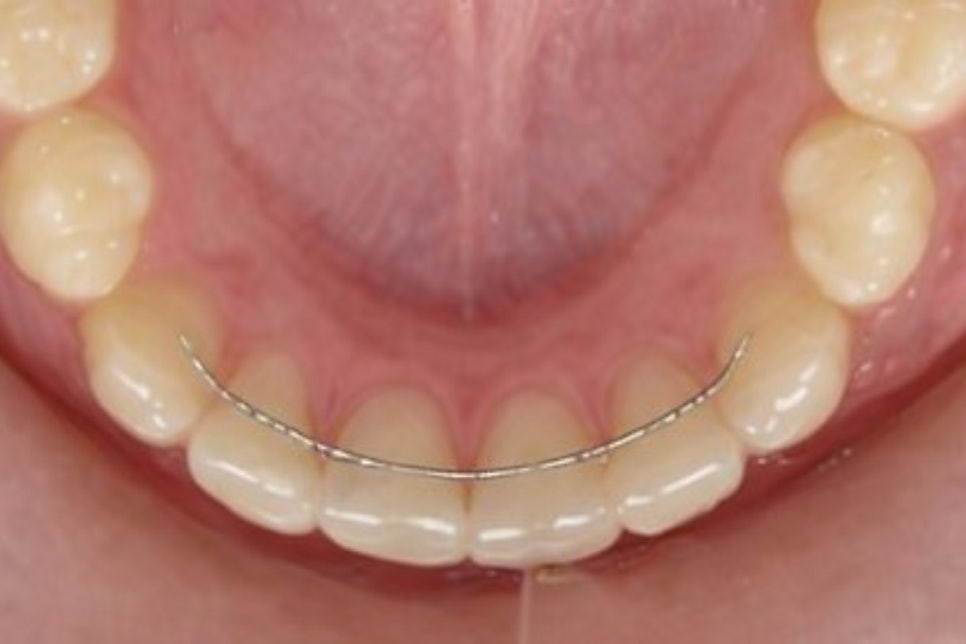

교정 장치를 착용 중인 분들 또한

음식물이 끼기 쉬운 환경 탓에

보다 자주 내원하는 것을 권해 드립니다.